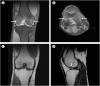

Regional Migratory Osteoporosis

Keywords: 25-OH-D3; Bisphosphonates; Hip; Knee; Transient Osteoporosis.